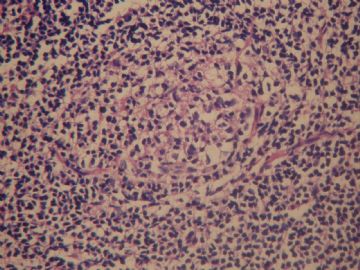

简要病史:  女   55岁临床病史:发现左颈淋巴结肿大一周,双颈及腋下可扪及多个肿大淋巴结.

手术所见:胸锁乳突肌深面多个肿大淋巴结,成簇、质中等、与周围无粘连。

巨检:淋巴结一个,1.3×0.7×0.6cm,切面灰白。

髓索和窦境界分明,滤泡萎缩,考虑为T区反应性增生。

生发中心退行性转化,castlamen病

淋巴窦明显扩张,窦内组织细胞增生,存在次级淋巴滤泡,应该是淋巴结反应性增生(以窦组织细胞为主)。

老年女性,全身多发 淋巴结肿大,图1见深染区和浅染区,图2 和3见生发中心血管植入,呈蚊香样结构,图4,5见组织细胞增生,未见吞噬现象,淋巴结髓索和窦境界存在,见滤泡结构,首先考虑淋巴结反应性增生病变(窦性增生),但要排除castlamen病可能,浆细胞不明显